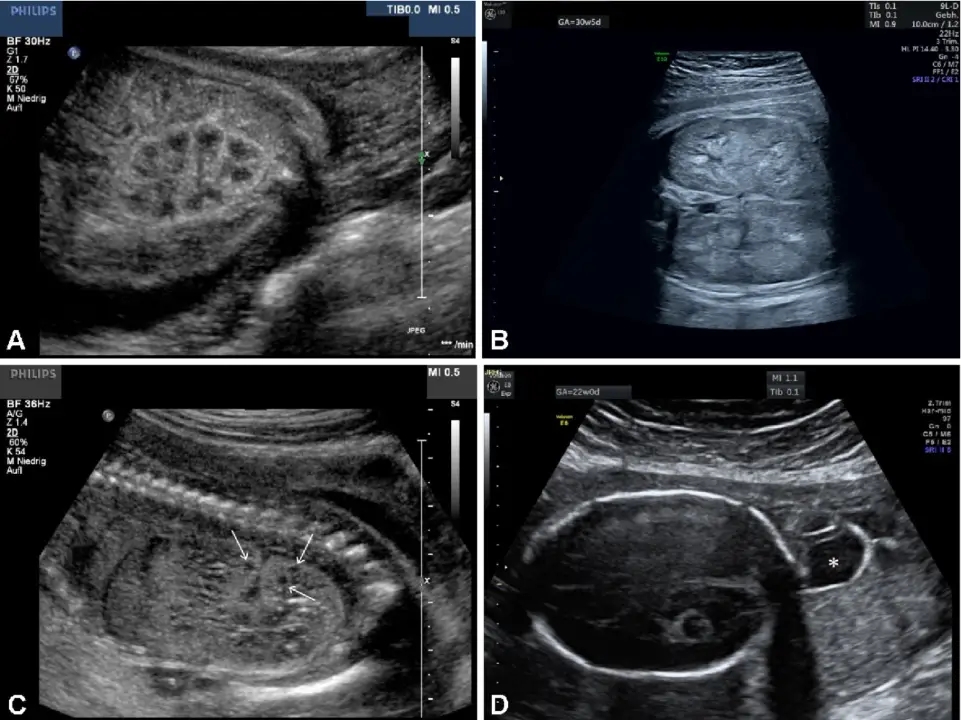

نشانههای احتمالی مشکلات جنینی

برخی از شاخصهای غیرنرمال میتوانند به نشانههایی از ناهنجاریهای جنینی اشاره کنند، مانند:

- NF در سونوگرافی انومالی: NF یا ضخامت پشت گردن، یکی از شاخصهای مهم در سونوگرافی آنومالی است. این عدد نشاندهنده ضخامت بافت پشت گردن جنین است که اندازهگیری میشود. افزایش ضخامت NF میتواند نشانه احتمال ناهنجاریهای کروموزومی مانند سندروم داون باشد.

- اختلالات رشد جنین: اگر اندازههای جنین کوچکتر یا بزرگتر از حد معمول باشد، ممکن است نشاندهنده مشکلاتی مانند رشد کند داخل رحمی (IUGR) یا ماکروزومی باشد.

- نقایص ساختمانی: اندازههای غیرطبیعی در ساختارهایی مانند مغز، قلب، ستون فقرات و اندامها میتواند نشانهای از ناهنجاریهای مادرزادی باشد.

- مایع دور جنین یا ناهنجاری در جفت: تجمع غیرطبیعی مایع یا مشکلات جفت میتواند روی رشد جنین تأثیر بگذارد.

- مشکلات ژنتیکی و کروموزومی: برخی از اختلالات ژنتیکی ممکن است با نشانههای خاصی در سونوگرافی انومالی دیده شوند.